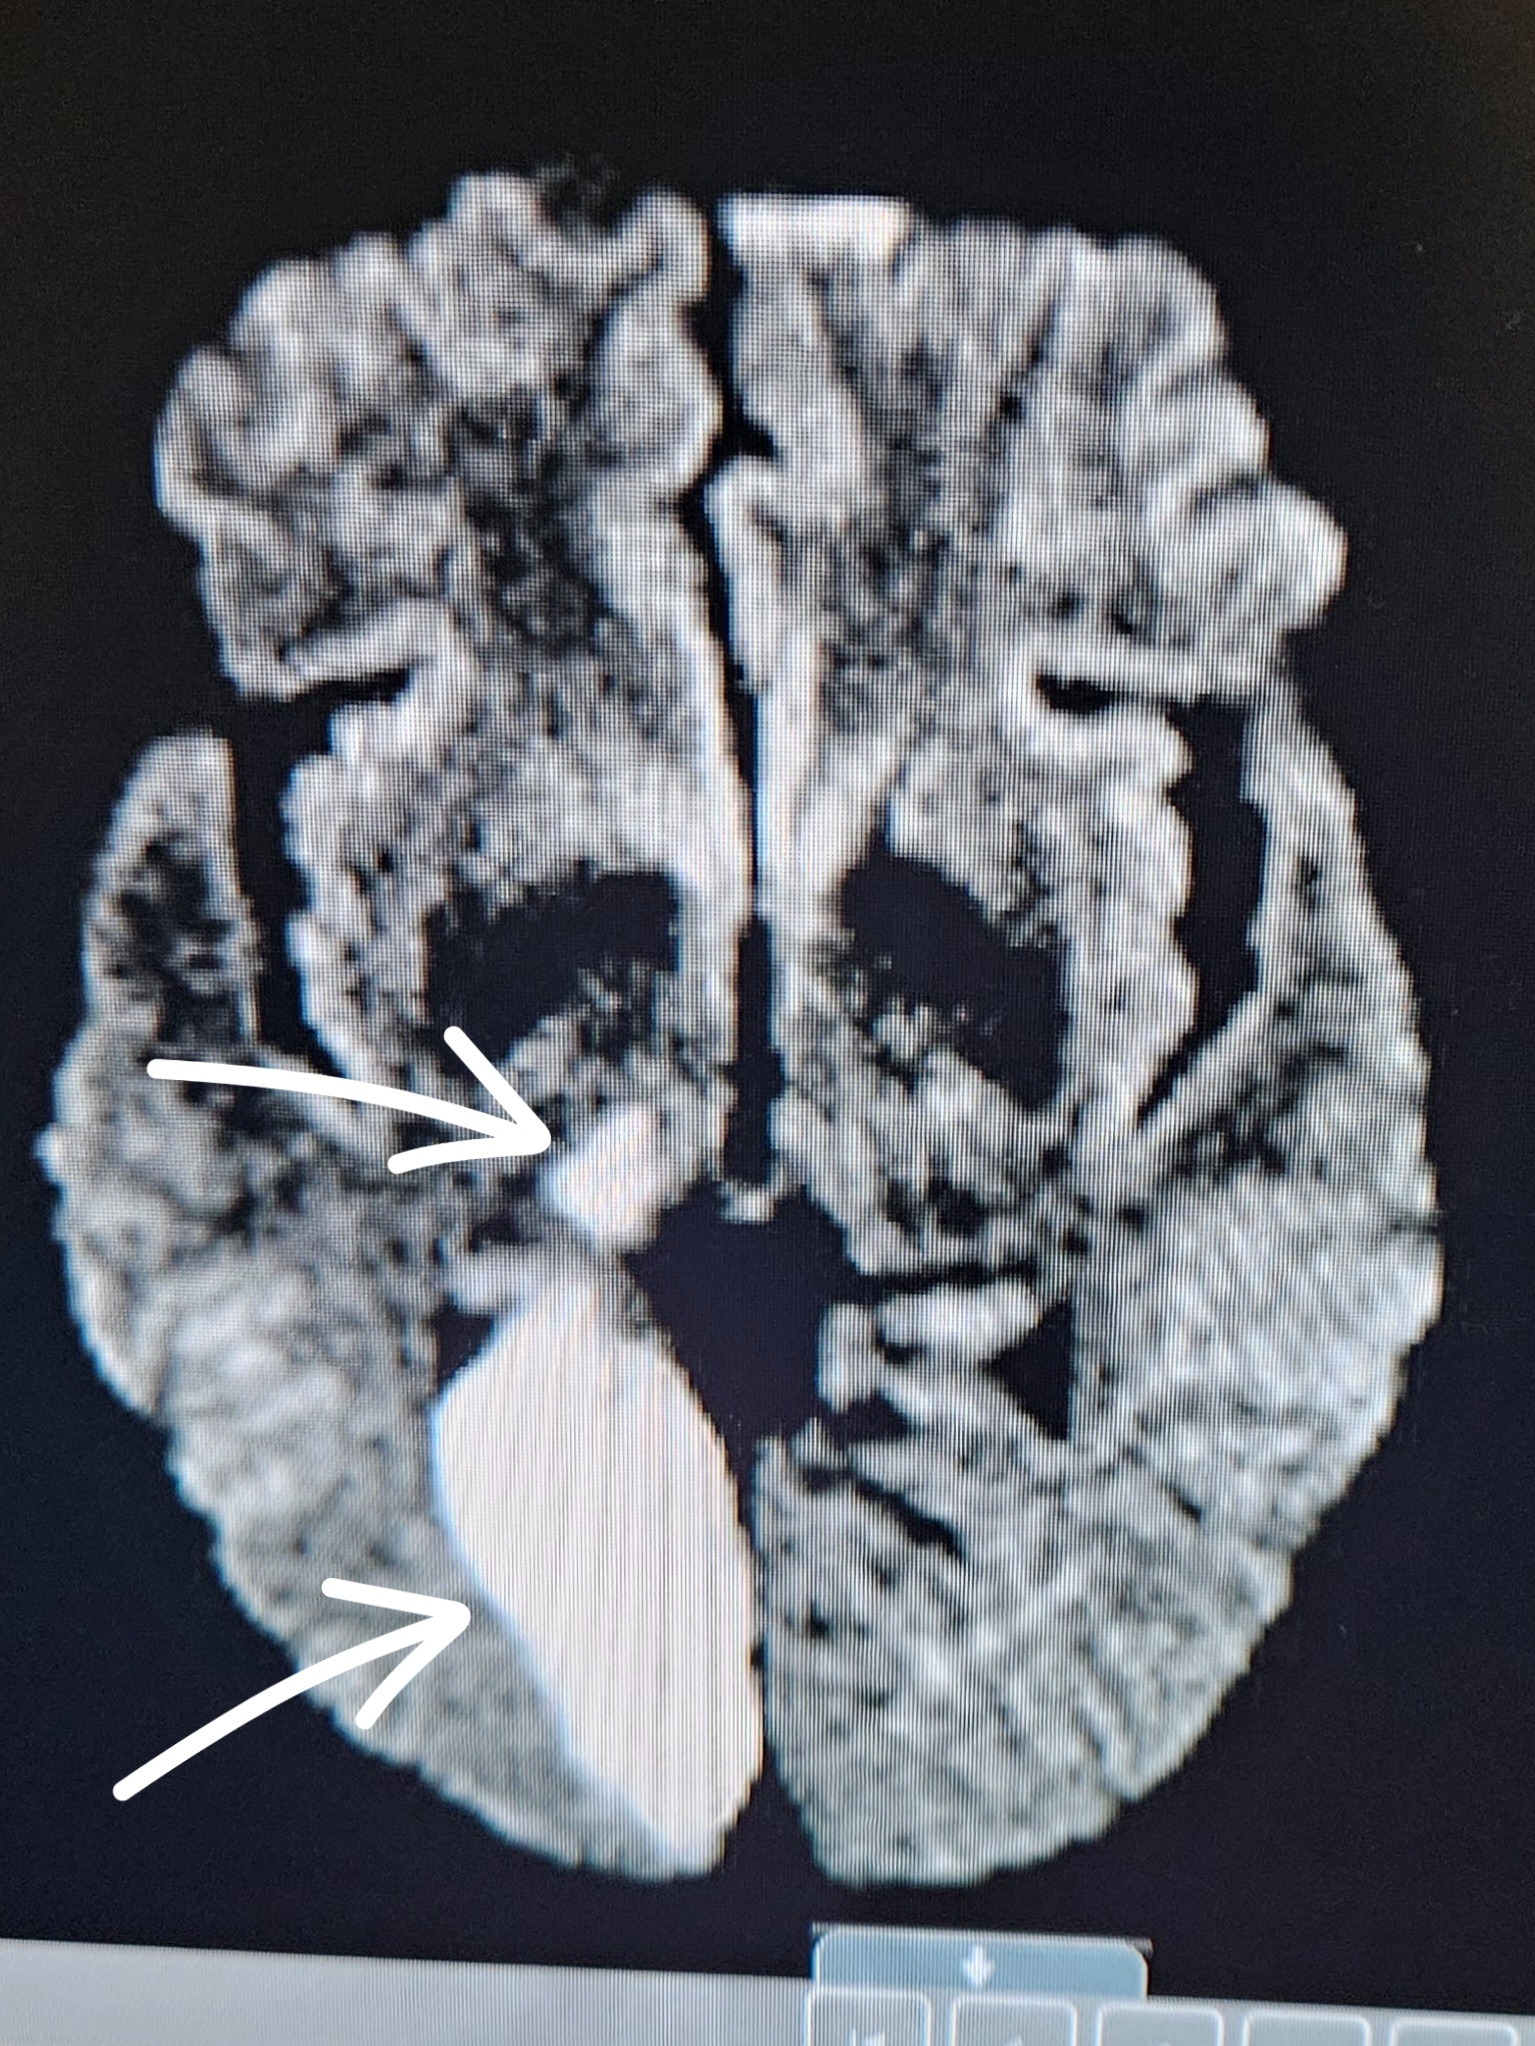

My name is Richard, and I am reaching out for support after recently suffering a stroke. This unexpected event has changed my life in many ways, especially by limiting my ability to work due to vision and mobility issues. A part of my brain has been damaged by the stroke which affects the right side pf my body, including my vision. This is making it difficult for me to drive around, attend medical appointments, and manage daily tasks that I once took for granted.